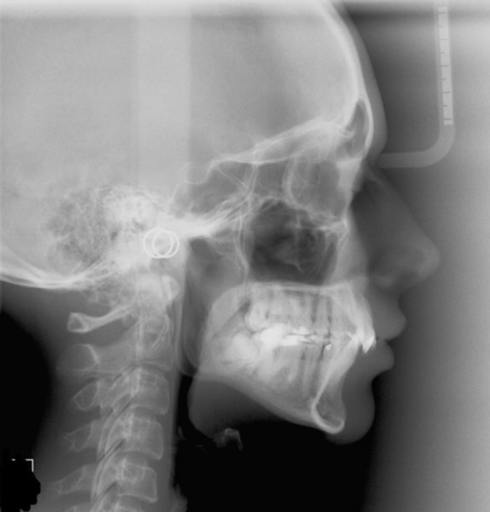

I am a 25 year old female and I have quite a noticeable asymmetry on my left mandibular region. i consulted a few orthoointists who deal with maxillofacial surgeons and they asked me to go with orthognatic surgery but for reducing the prominence of the lower jaw and say not much about my asymmetry. According to one of the orthodontists I have a rather concave mandible angle on one jaw(from the skeletal images) and convex on the other and I would need an implant to produce the curve at the angle and has therefore suggested for me to go with orthodontics for a proper bite and later a bone implant on the left mandible as a less invasive procedure. I was wondering on the other hand if there are some dentofacial appliances that can be used to expand my left jaw region as the teeth seem to be a little depressed inside too. Also, is there anything available to expand the jaw too (as in the bone)? I have uploaded some pics on the link https://www.dropbox.com/sh/8tdf6dveihneo95/5LcrqKMnKj also, do i really require a lower mandible reduction?